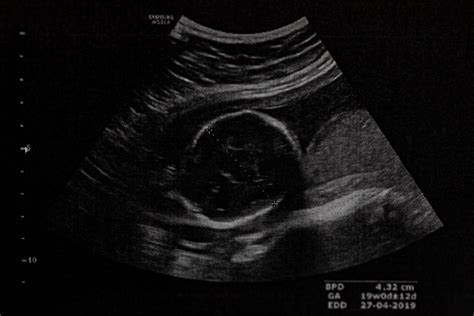

Dieťa v maternici začína skúmať samo seba ešte pred tým, ako začne aktívne komunikovať s matkou. Siaha si na tvár, zíva a občas aj čká. Približne od 20. týždňa tehotenstva začína matka pociťovať prvé pohyby, známe ako "kopanie" nožičiek. U žien, ktoré už rodili (druhorodičky), sa tieto pohyby často objavujú o niečo skôr, v priemere o dva týždne. Je to dané tým, že už majú skúsenosti s rozpoznávaním týchto pohybov a ich brušná stena môže byť citlivejšia. Ak má matka placentu umiestnenú na prednej strane maternice, môže tieto pohyby vnímať tlmenejšie.

Je veľmi individuálne, kedy žena po prvýkrát pocíti pohyby bábätka. Často si ich na začiatku môže zamieňať s inými pocitmi v bruchu či žalúdku. Prvé kopance sa zvyčajne objavujú v druhom trimestri, medzi 16. a 20. týždňom tehotenstva. Ak žena tieto pohyby necíti ani v tomto období, mala by to konzultovať s lekárom, pretože plod by sa v maternici mal hýbať.

Odborníci však zistili, že dieťa začína s pohybmi končatín oveľa skôr, hneď ako sú jeho končatiny vyvinuté. Tieto pohyby sú však vtedy tak malé, že ich matka ešte necíti. Až keď plod zosilnie a jeho pohyby sú výraznejšie, matka ich začne vnímať. Preto niektoré vnímavé ženy môžu cítiť pohyby aj pred 16. týždňom.

Štúdie ukazujú, že aj malý plod v brušku dokáže vyvinúť prekvapivo veľký tlak. V 20. týždni tehotenstva môže tlak dosahovať približne 311 pascalov, v desiatom týždni sa zvyšuje na viac ako 500 pascalov. Tesne pred pôrodom, v 35. týždni, táto aktivita výrazne klesá na približne 150 pascalov, čo je spôsobené predovšetkým obmedzeným priestorom v maternici.